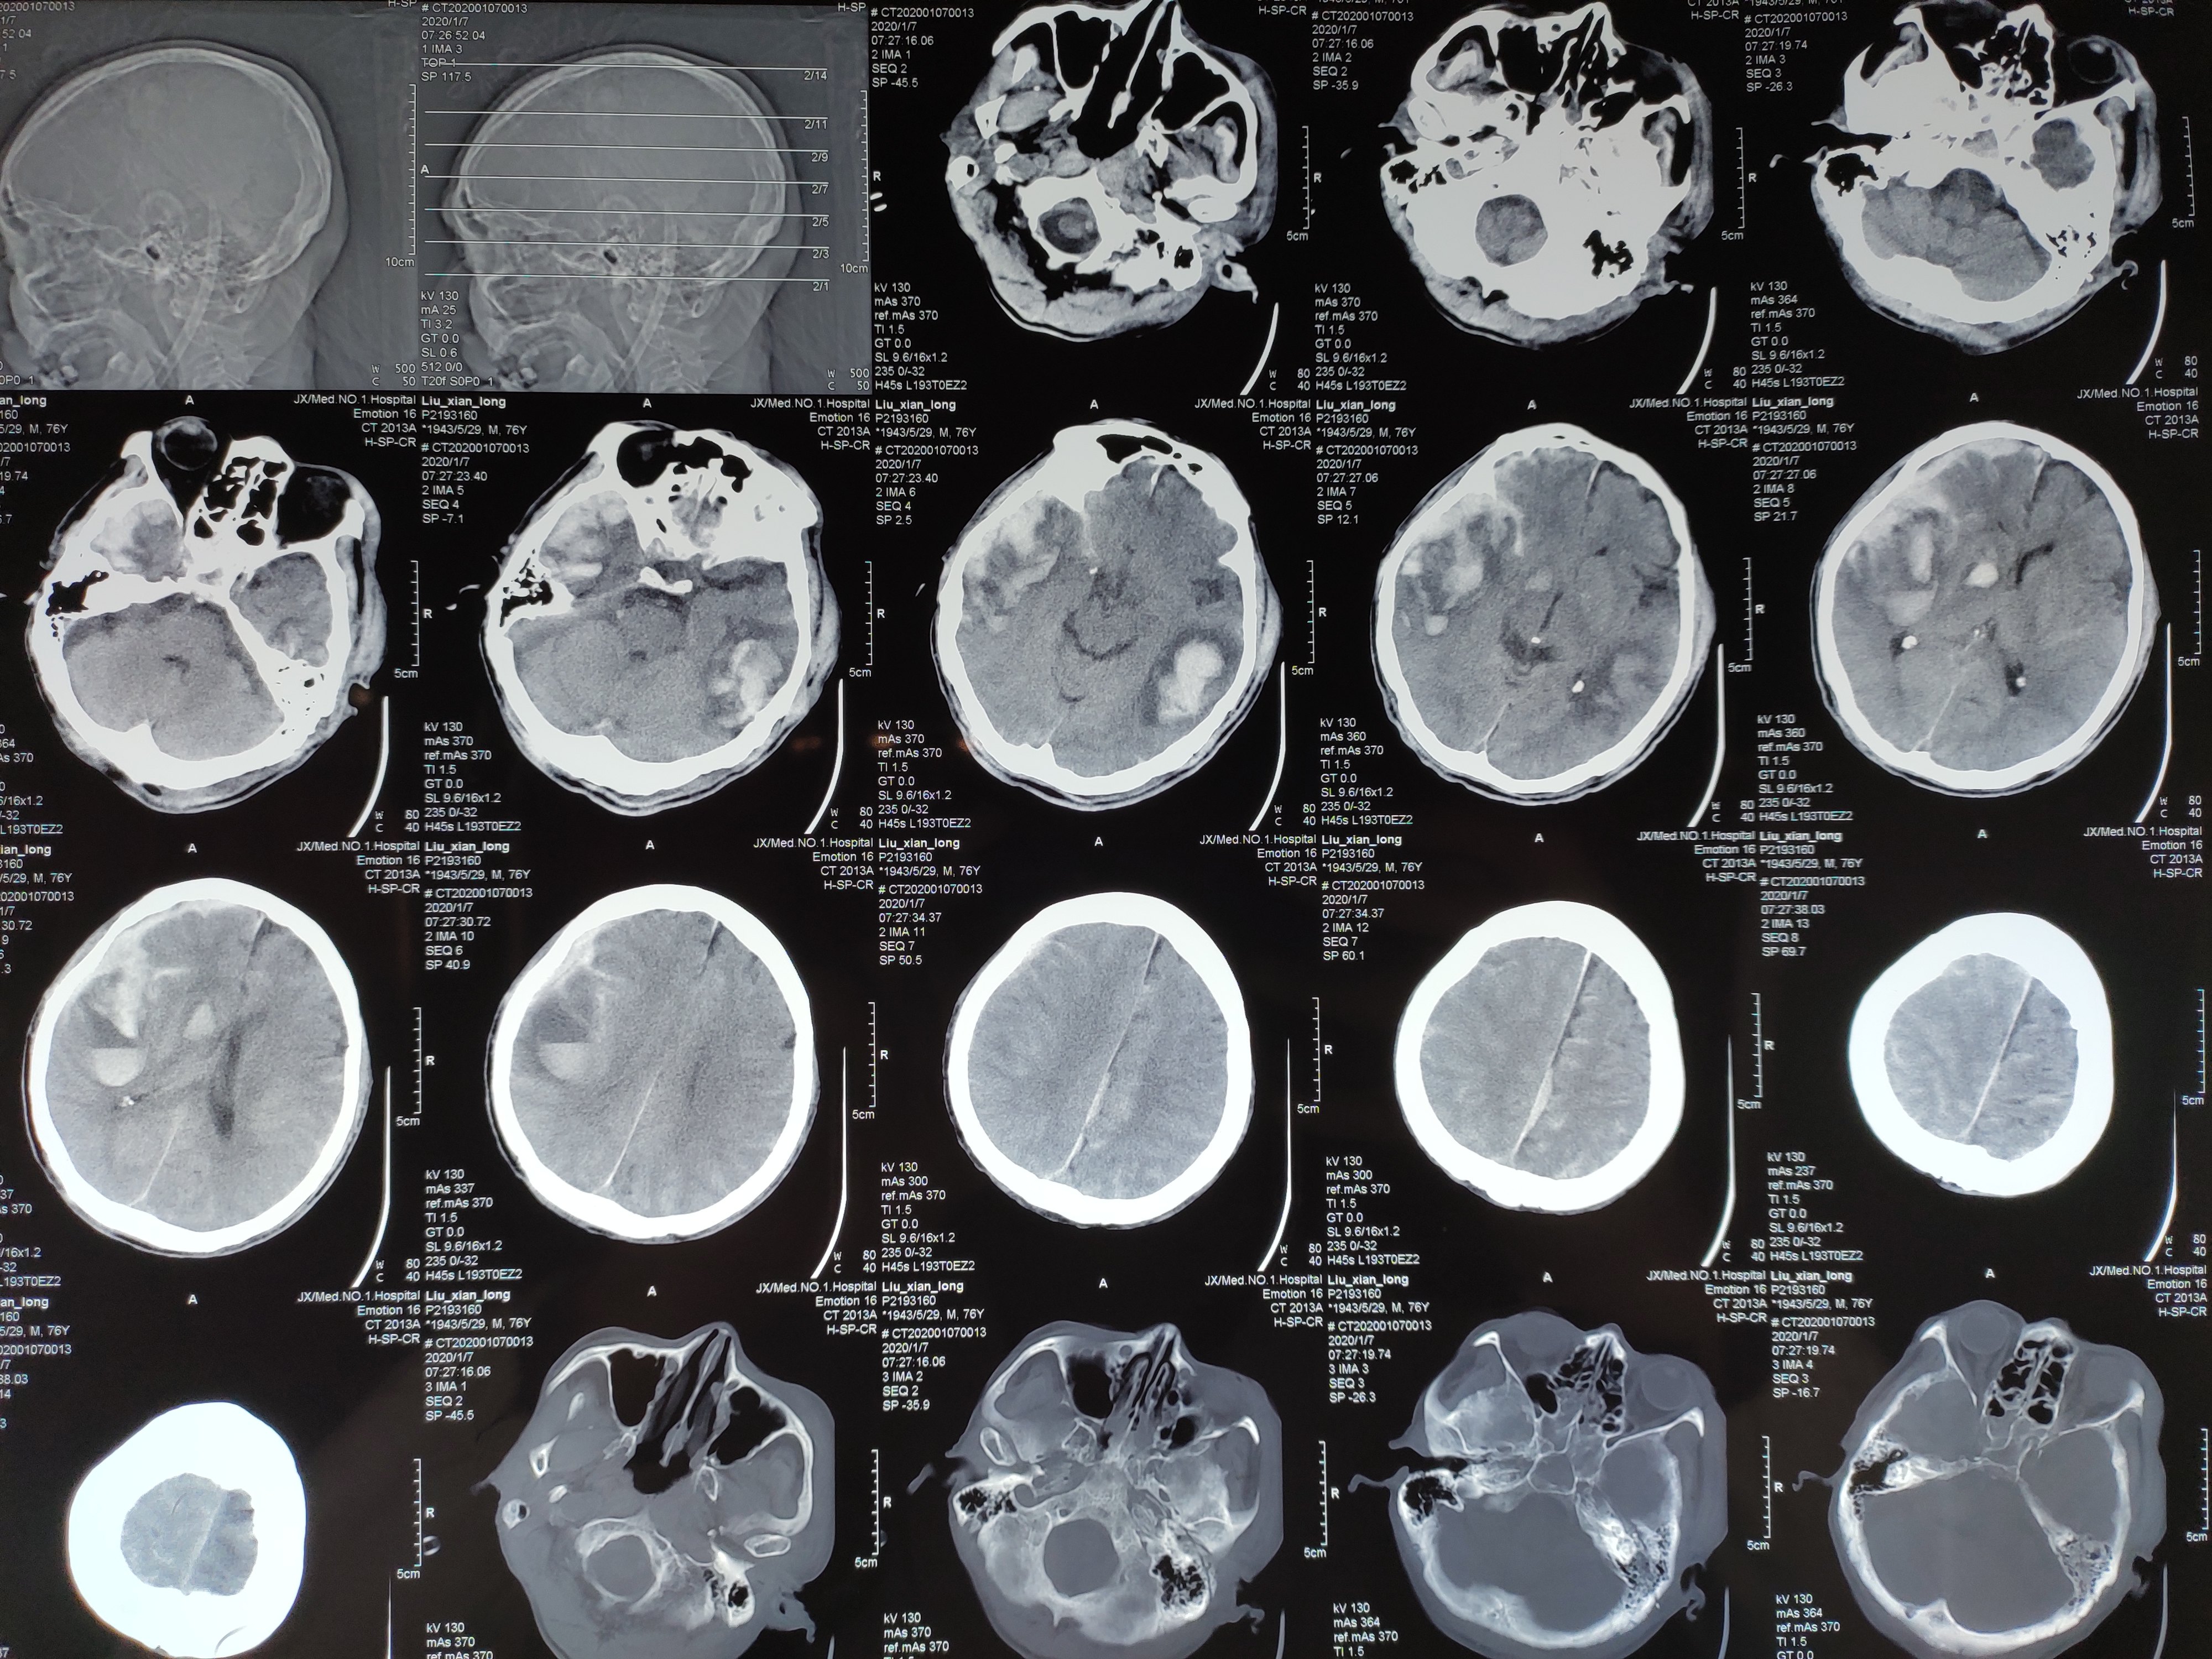

高血压脑出血 - 好大夫在线

图片尺寸4000x3000

车祸多发脑出血,开刀成功 - 好大夫在线